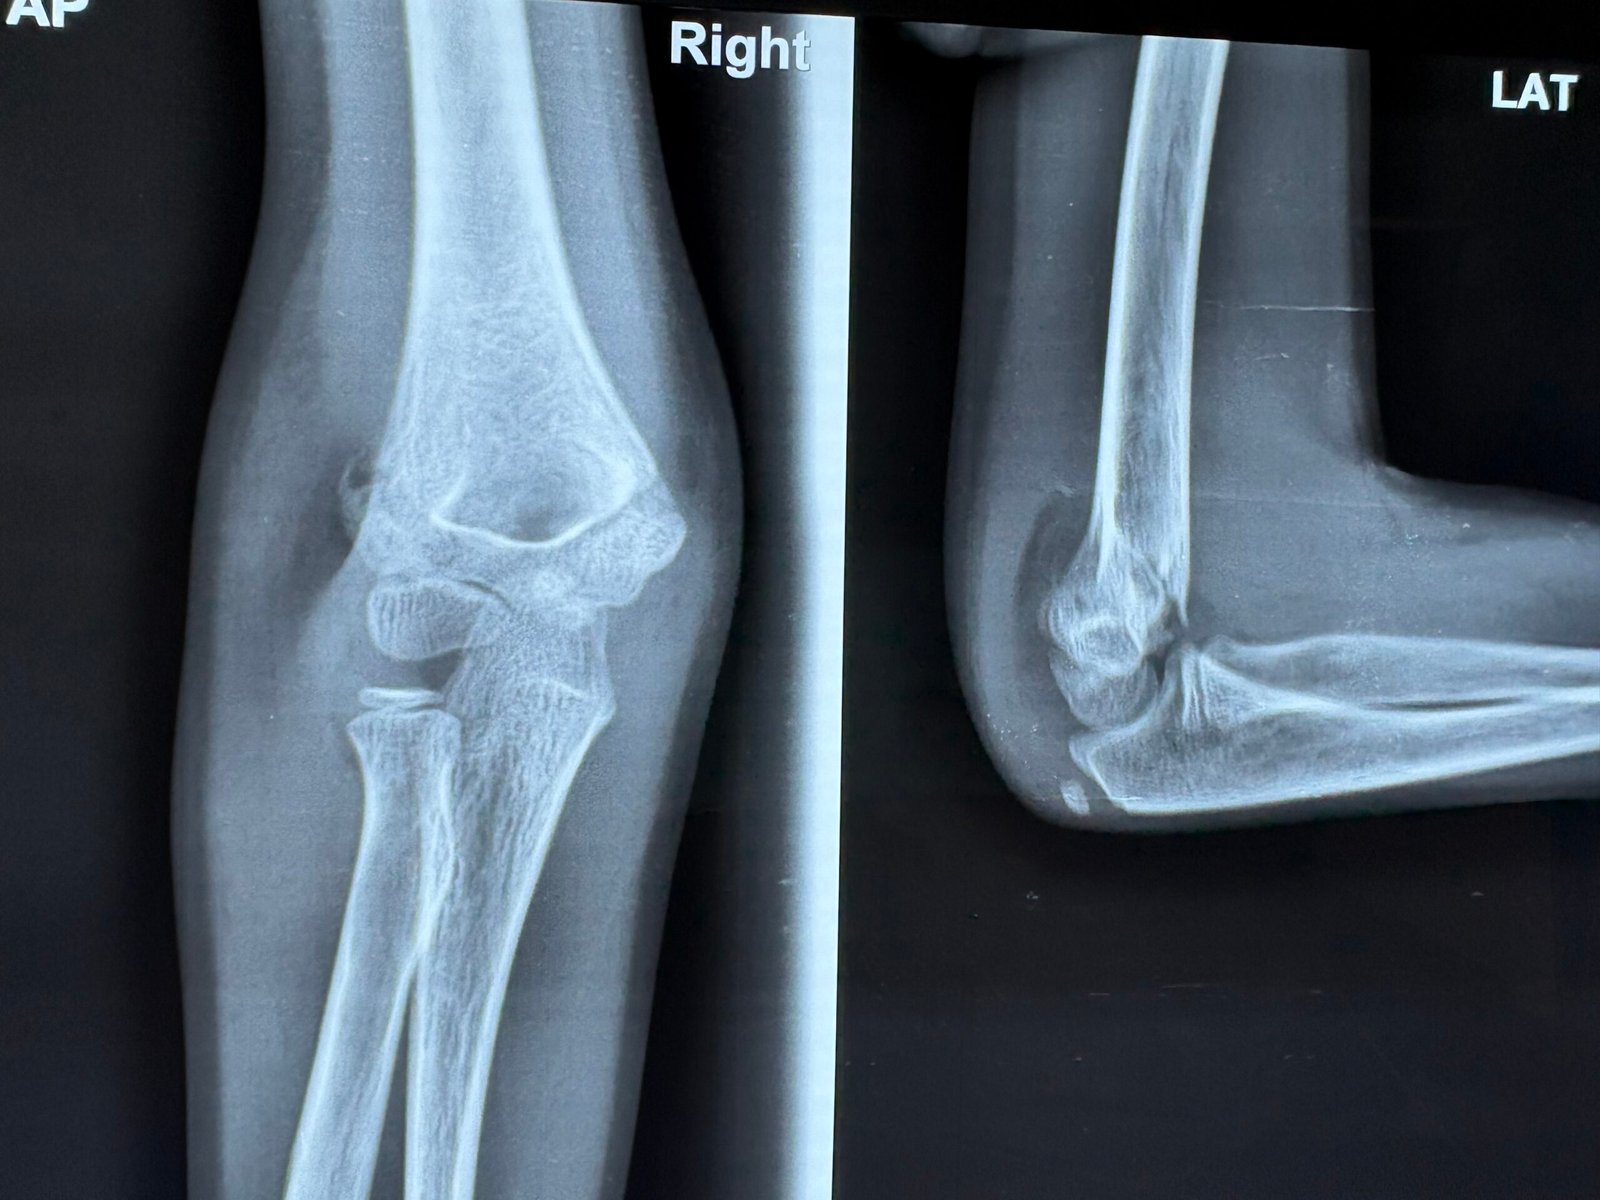

Accident & Trauma Care – Specialized in Bone & Joint Injuries.

- Trauma & Fracture:

Emergency Bone Care.

Over 8,000 successful orthopedic procedures, ranging from complex trauma to total joint replacements.